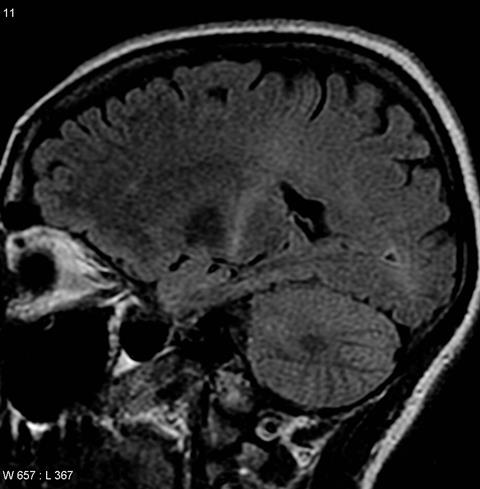

- ALS similarities. The CC023 mice showed physical symptoms and lesions very similar to those seen in humans with ALS.

In short, the initial viral infection spread and infected the lumbar spinal cord early on, triggering an immune reaction, lesions and signs of illness. The virus was cleared over time, but the lesions and clinical symptoms persisted, and in the CC023 strain these signs resembled ALS-like disease.